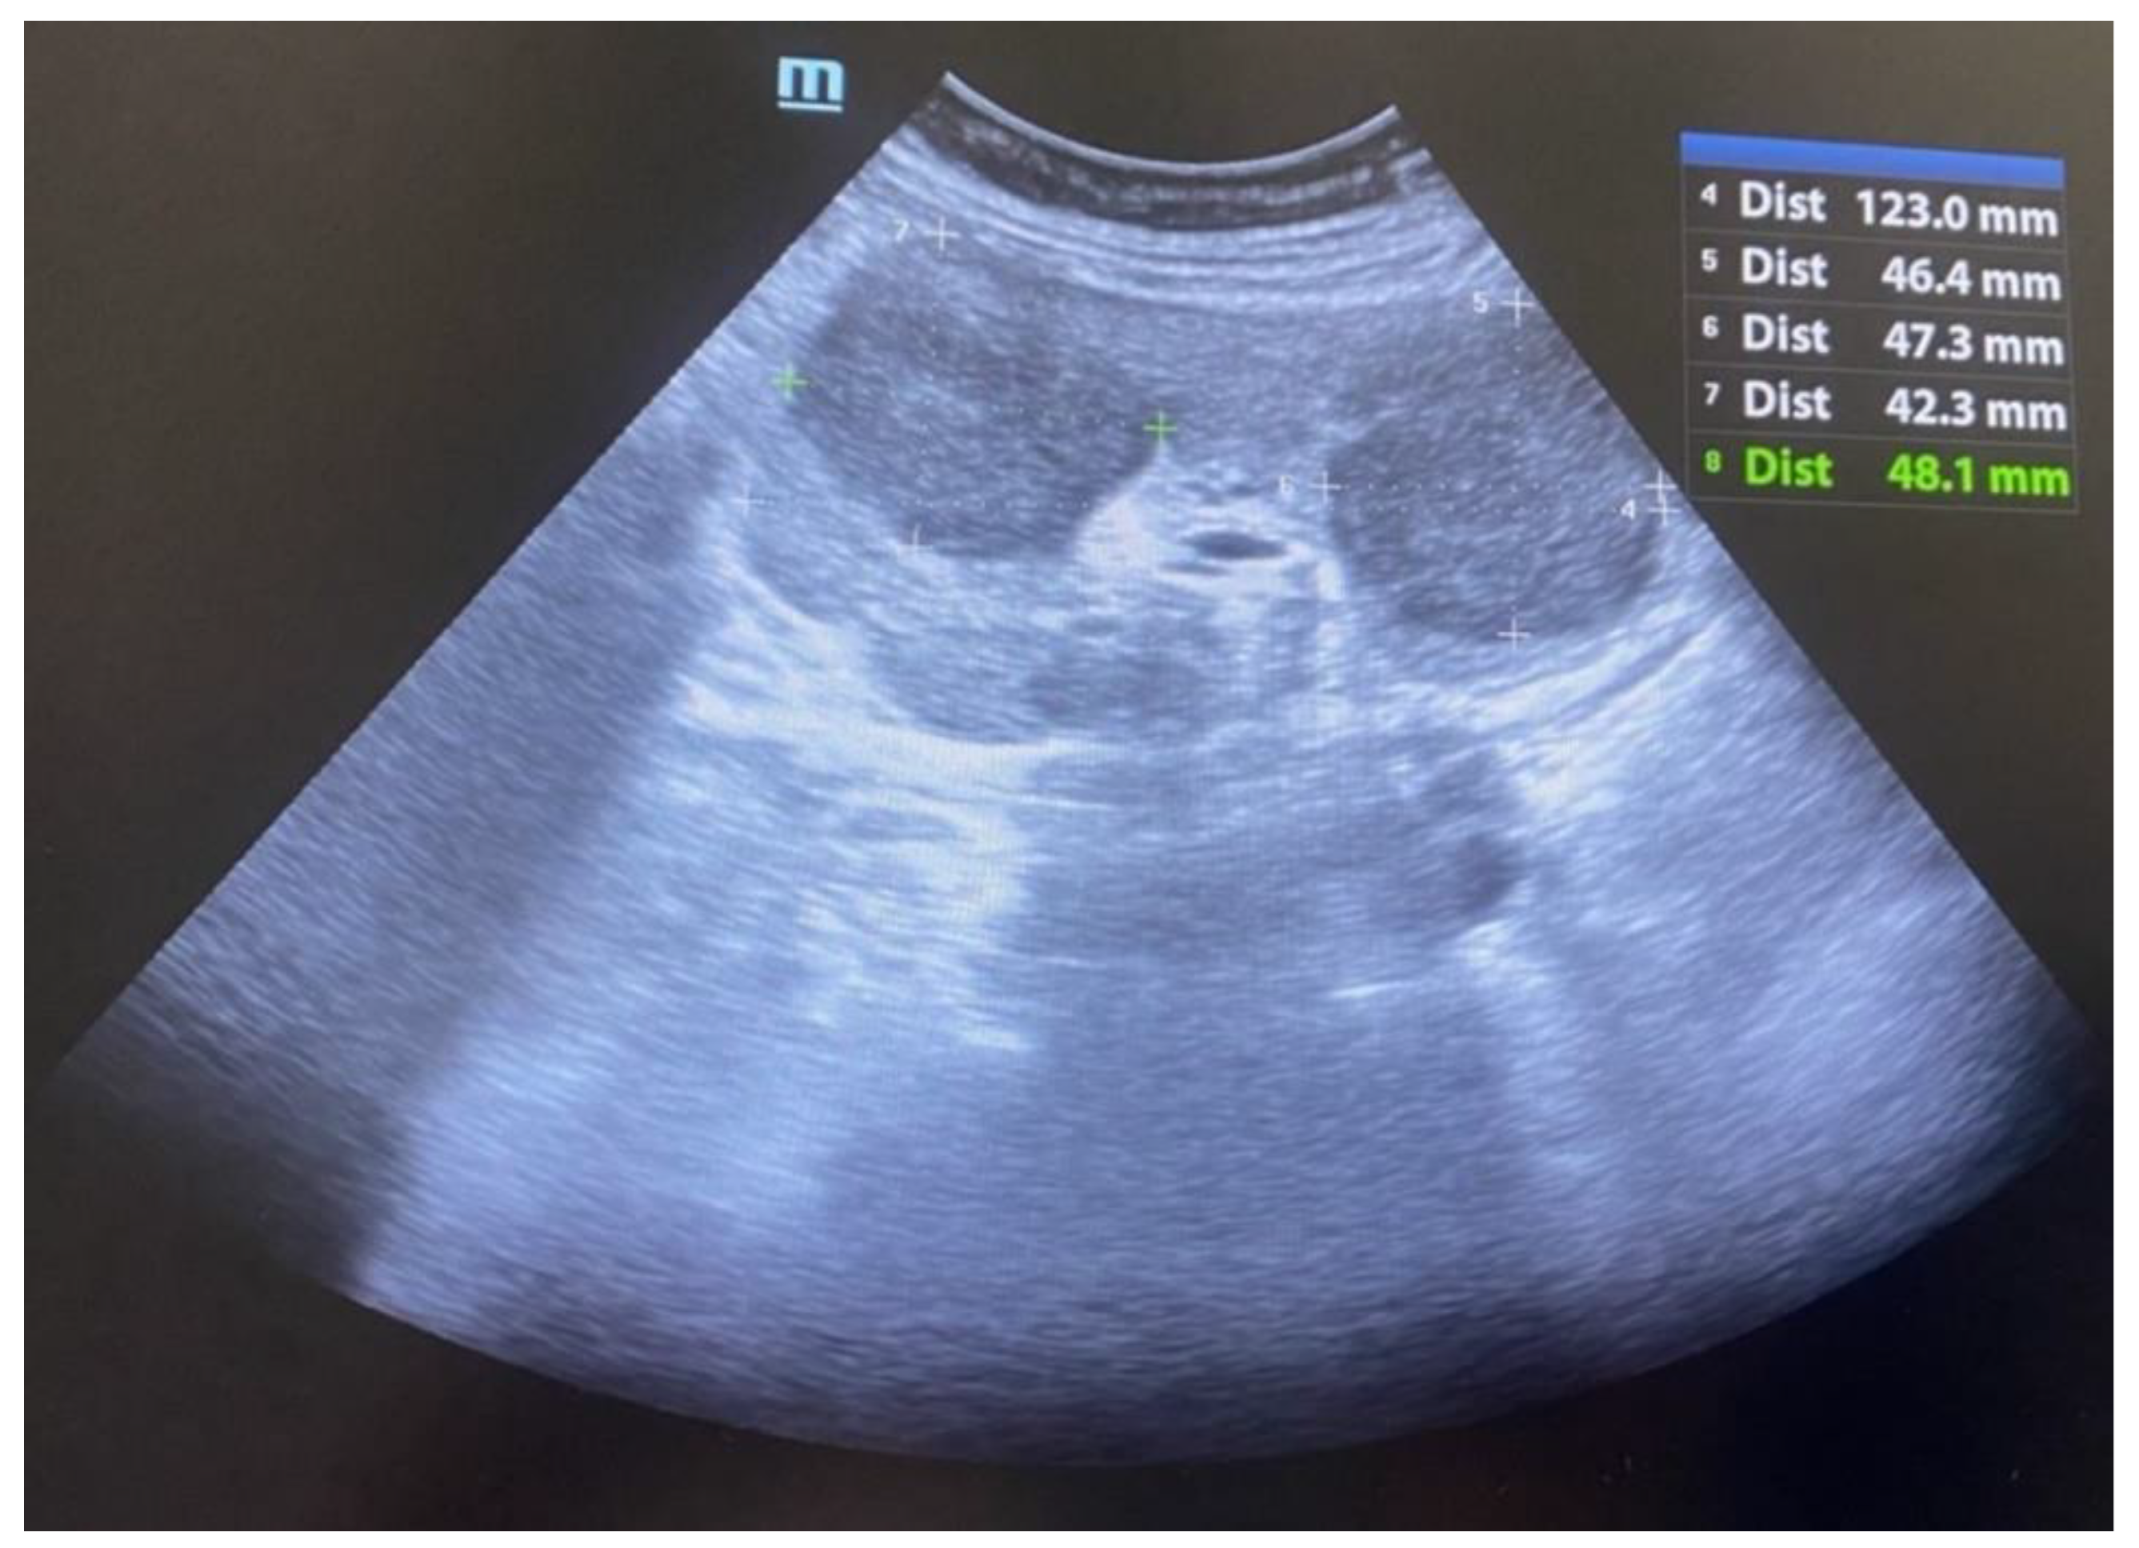

During hospitalization, an ultrasound of the transplant kidney was preformed and after the registered three infiltrative circular lesions isoechoic with parenchyma, a CT scan was also performed using CT-GE Medical Systems, LCC, Revolution HD, Belgrade, Serbia, revealing three lesions in the transplanted kidney, a larger lesion in the body of the pancreas, and additional lesions in the native kidneys (Figure 1, Figure 2 and Figure 3). Additionally, a lesion was identified in the medial lobe of the right lung adjacent to the sixth rib cartilage.

Figure 3. CT image: post-transplant lymphoma in a kidney allograft.